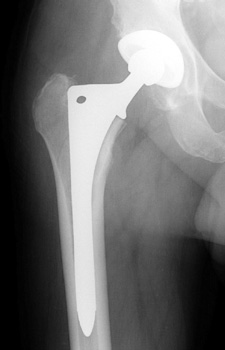

Control perforation lateral femoral cortex, reduced by cerclage cables. A control perforation of the lateral femoral cortex was performed in this revision total hip replacement to facilitate removal of the old femoral prosthesis. It is reduced by cerclage cables.